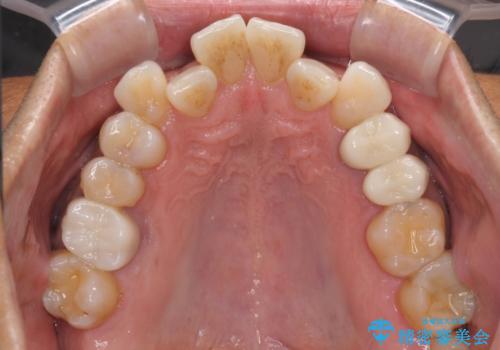

腫れもなくなり、見た目もきれいになったため、右上もご希望されて計3本の歯を治療しました。患者様には大変満足して頂きました。

左上で効果を実感して頂き、その後右上もご希望されました。合計3本の歯を治療しました。